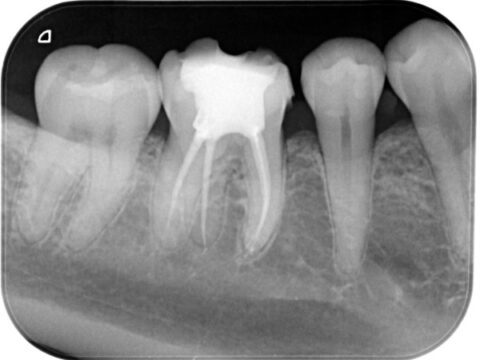

0219-001_Af3